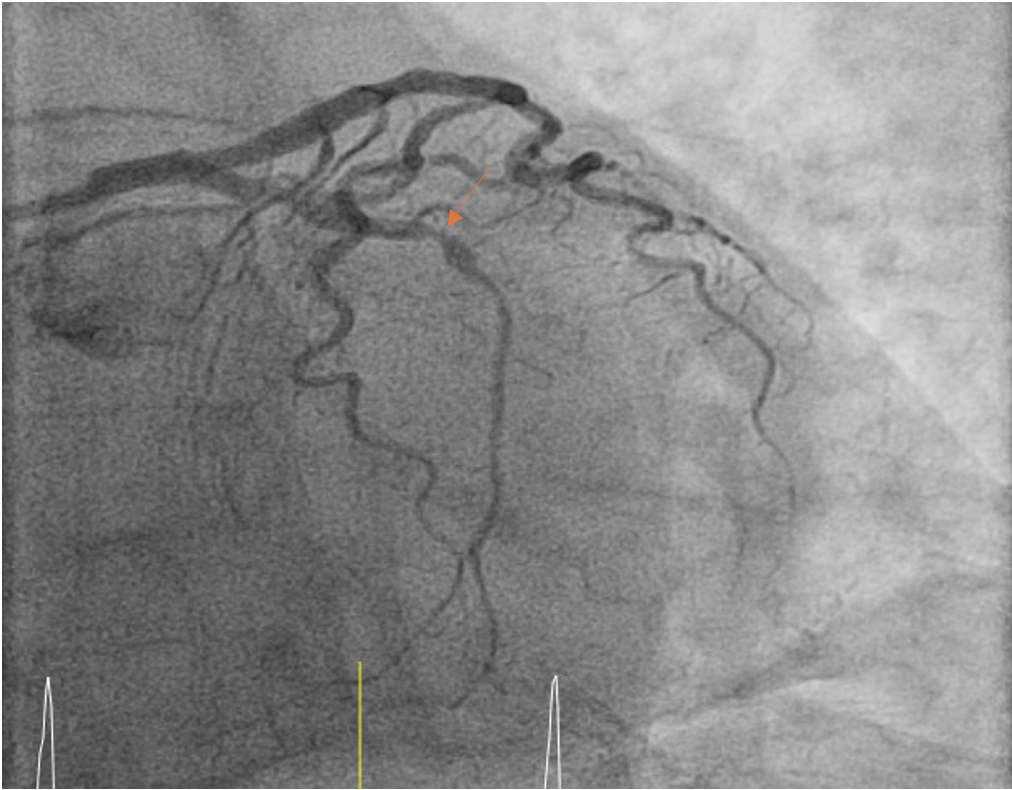

The post-PCI angiogram shows successful re-vascularization of LCx.